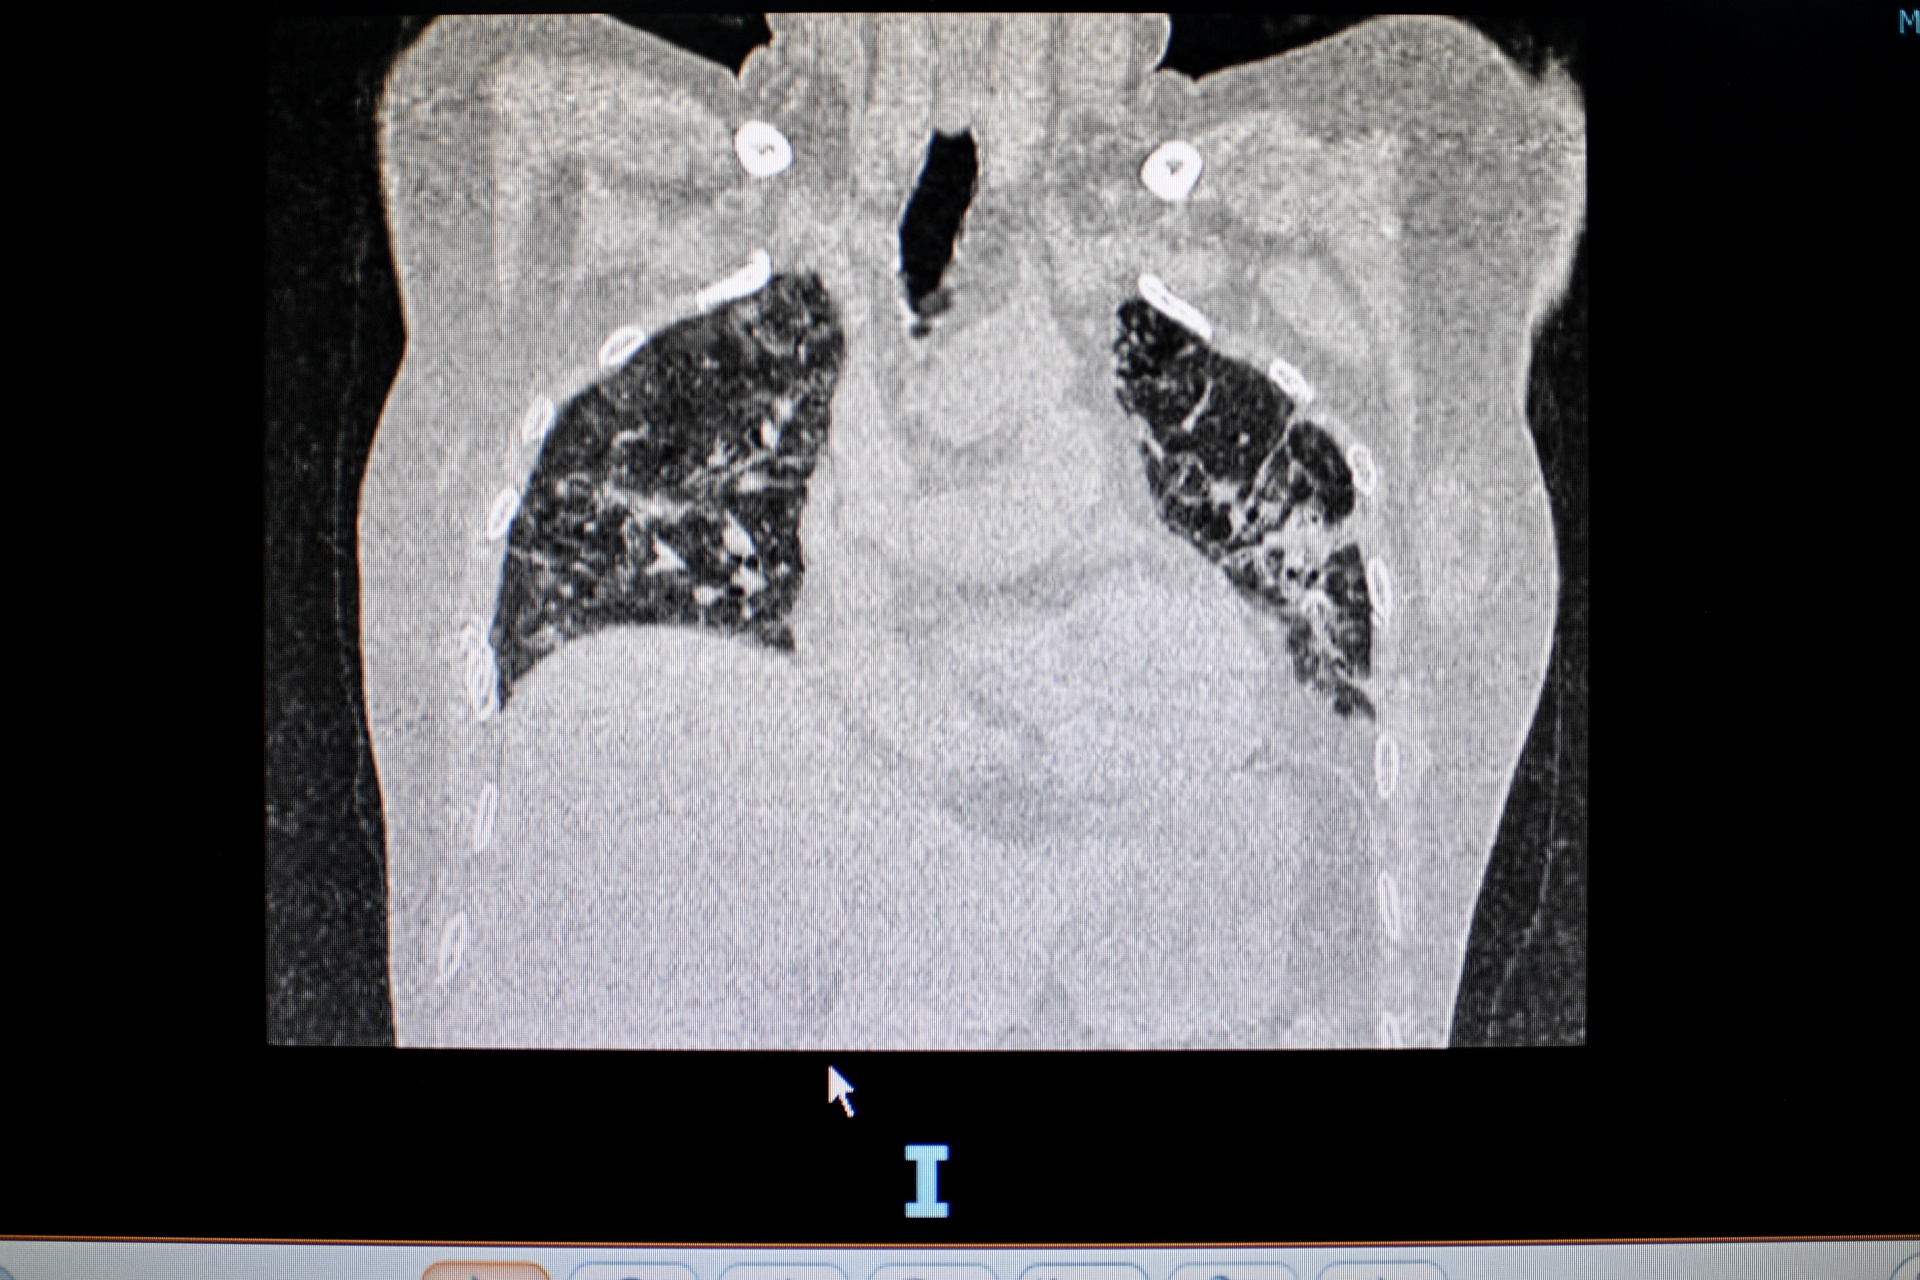

Bác sĩ Nguyễn Hải Công kiểm tra phim chụp phổi của một bệnh nhân điều trị di chứng hậu Covid-19. Ảnh: Bích Huệ.

Trên phim chụp phổi cắt lớp vi tính, các bác sĩ phát hiện người đàn ông bị tổn thương phổi dạng xơ hóa, giãn phế quản. Đây là di chứng vĩnh viễn, dù điều trị nhưng khó trở về bình thường.

Phim X-quang phổi của bệnh nhân 52 tuổi, bị suy hô hấp nặng sau khi khỏi Covid-19. Ảnh: Duy Hiệu.

Mới đây nhất, một phụ nữ 52 tuổi đến khám trong tình trạng suy hô hấp mạn tính, phải mang theo bình oxy dù khỏi Covid-19 gần một tháng. Trên phim X-quang, hai bên phổi của bệnh nhân mờ đục, diện tích tổn thương nhiều.